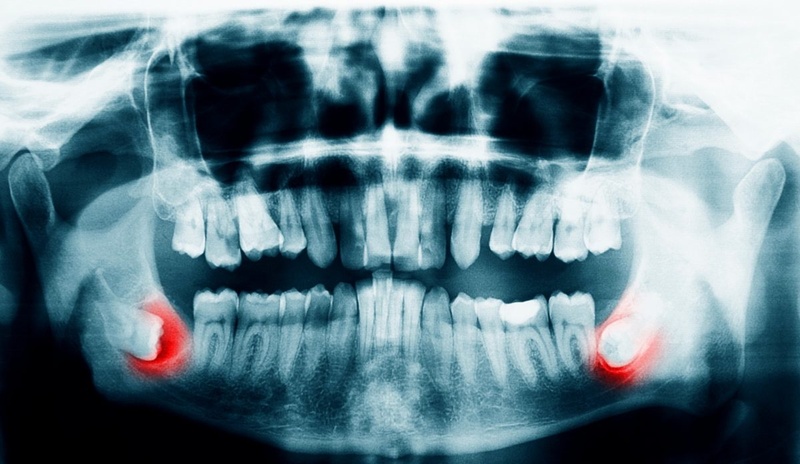

Nhổ răng khôn mọc lệch là một trong những thủ thuật nha khoa phổ biến ở người trưởng thành, đặc biệt là trong giai đoạn từ 17 – 25 tuổi, thời điểm răng khôn (răng số 8) bắt đầu mọc. Do thiếu khoảng trống trên cung hàm, răng khôn thường mọc lệch, mọc ngầm hoặc xoay hướng bất thường, gây ra hàng loạt vấn đề như đau nhức, sưng viêm, sâu răng và viêm nha chu.

Nếu không được xử lý sớm, răng khôn mọc lệch có thể làm tổn thương răng số 7, gây tiêu xương hàm hoặc hình thành u nang quanh răng. Bài viết dưới đây sẽ giúp bạn hiểu rõ khi nào cần nhổ răng khôn, quá trình nhổ có đau không, có nguy hiểm không và cách chăm sóc sau khi nhổ để phục hồi an toàn.

Nếu răng khôn mọc lệch nhưng không đau, vẫn nên đến nha khoa để chụp X-quang kiểm tra. Bởi nhiều trường hợp răng khôn mọc lệch 90 độ hoặc mọc ngầm dù không đau vẫn gây tiêu xương hàm, sâu răng số 7 hoặc hình thành u nang theo thời gian. Chỉ khi răng mọc đúng hướng, nướu khỏe và dễ vệ sinh mới có thể giữ lại và theo dõi định kỳ.

- Thăm khám tổng quát: Bác sĩ sẽ kiểm tra tình trạng răng miệng, khai thác tiền sử bệnh lý toàn thân và các loại thuốc bạn đang sử dụng. Chụp phim X-quang xác định chính xác vị trí, hướng mọc, hình dạng chân răng và mối liên hệ với các cấu trúc quan trọng như dây thần kinh.